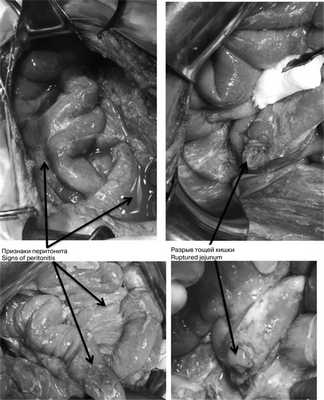

В экстренном порядке выполнена диагностическая видеолапароскопия. При ревизии в брюшной полости около 1000 мл мутного содержимого во всех отделах. Париетальная и висцеральная брюшина тусклая, с наложением фибрина, гиперемирована. При ревизии париетальной брюшины передней брюшной стенки в левом подреберье визуализирован дефект париетальной брюшины и разрыв внутренней косой, поперечной мышц без активного кровотечения размером 4×3 см. Принято решение о конверсии — выполнена широкая срединная лапаротомия. При ревизии тонкой кишки непосредственно за связкой Трейца обнаружен разрыв тощей кишки на 1/3 по противобрыжеечному краю (рис. 2), Рис. 2. Признаки перитонита и разрыва тонкой кишки (интраоперационные фотографии). при осмотре сальниковой сумки выявлено геморрагическое пропитывание парапанкреатической клетчатки. Выполнена назоинтестинальная интубация. Произведена мобилизация участка тощей кишки из-под связки Трейца с иссечением краев разрыва стенки тощей кишки, ушиванием разрыва тощей кишки в поперечном направлении двухрядным швом. Прядь большого сальника фиксирована к линии швов на тощей кишке. Выполнена санация брюшной полости 4 л 0,9% раствора NaCl. Ушит травматический разрыв мышц передней брюшной стенки, двухпросветный дренаж оставлен в ране, выведен через контрапертуру на переднюю брюшную стенку. Двухпросветные дренажи также установлены в подпеченочное пространство справа, в полость малого таза, в левый латеральный канал. С целью дренирования полости сальниковой сумки установлен однопросветный дренаж.

При динамическом наблюдении отмечено нарастание явлений геморрагического шока. С учетом клинико-инструментальной картины заболевания закрытой травмы живота с повреждением внутренних органов и продолжающимся внутрибрюшным кровотечением в экстренном порядке выполнена лапаротомия. Во время доступа в брюшную полость выявлено, что кожа и подкожная клетчатка полностью отсепарированы от подлежащего слоя прямых и косых мышц, имбибированных кровью из-за размозжения (межмышечная гематома) на всем протяжении доступа. Множественные более мелкие гематомы в подкожной клетчатке. В брюшной полости во всех отделах большое количество крови и сгустков (1800 мл), кровь аспирирована с помощью аппарата CellSaver. Продолжающегося активного кровотечения не выявлено. При ревизии органов брюшной полости: в проекции V—VI сегментов правой доли печени по краю выявлена подкапсульная гематома размером около 6×2 см, не пульсирующая, в объеме за время операции не увеличилась. Других повреждений печени по диафрагмальной и висцеральной поверхностям не установлено; на расстоянии 30, 40 и 45 см от связки Трейца 3 разрыва стенки тощей кишки с вскрытием просвета и 1 десерозированный участок. В области разрывов кишки также отмечены участки повреждения брыжейки тонкой кишки (рис. 3), Рис. 3. Разрывы петель тонкой и толстой кишки (интраоперационные фотографии). откуда продолжалось кровотечение. На расстоянии 60 см от связки Трейца выявлен полный поперечный разрыв тощей кишки с разрывом брыжейки кишки до уровня ее корня и активно продолжающимся кровотечением из сосудов брыжейки. Гематома в области брыжейки поперечной ободочной кишки, просвет кишки не вскрыт, гематома в размерах не увеличивается. Помимо этого гематома околокишечной клетчатки вдоль нисходящей ободочной кишки и сигмовидной кишки, брыжейка которой на уровне дистальной трети разорвана; сама сигмовидная кишка в области разрыва брыжейки не изменена, спастически сокращена, просвет не вскрыт, серозная оболочка обычной окраски с небольшими петехиальными кровоизлияниями из-за травмы. Обширная забрюшинная гематома по левому латеральному каналу с распространением на парааортальное клетчаточное пространство и корень брыжейки тонкой кишки. Париетальная брюшина в области левого латерального канала также разорвана, визуализирован левый мочеточник, без повреждений (моча концентрированная, макрогематурии нет). В области боковой стенки живота со стороны париетальной брюшины разрыв стенки размером около 10×5 см с повреждением прямых и косых мышц живота и продолжающимся низкоинтенсивным кровотечением из мышечных сосудов.